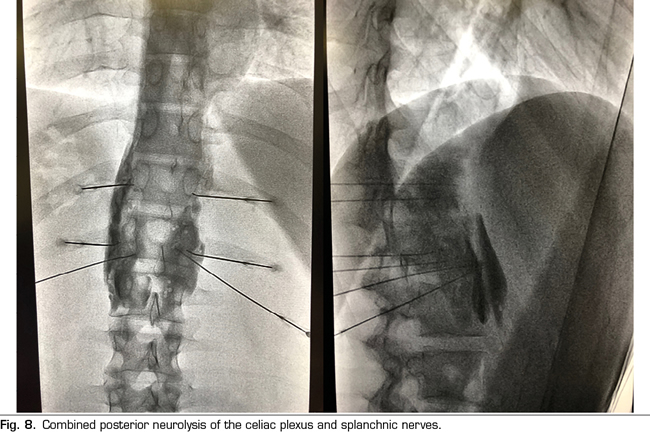

Following the conclusions of the previously described publications, an interventional treatment algorithm for patients with visceral pain associated with pancreatic cancer can be established (Figure 7). The standard procedure would be the posterior approach of the celiac plexus (classical approach), since today it continues being the one with the greatest scientific evidence, preferably transcrural and guided by fluoroscopy, due to its simplicity and speed. Ultrasound endoscopy would be indicated for neurolysis taking advantage of its diagnostic or therapeutic indication, for situations of inability to prone position, and as an alternative in case the posterior approach fails. Percutaneous ultrasound neurolysis would be reserved for selected cases, depending on the experience of the operator, since it is the technique that has fewer publications to date. We hope that in the future, studies allowing ultrasound-guided techniques, whether percutaneous or endoscopic ultrasound, will be published as the “reference method”, since they allow the visualization of surrounding structures with real-time injection control. An alternative to the blockage of the celiac plexus is the conventional radiofrequency of the splanchnic nerves, indicated when there is tumor infiltration of the celiac trunk, important anatomical alterations or if the celiac plexus neurolysis fails. It is also possible to consider a combined neurolysis - neurolytic blockade of the celiac plexus associated with neurolytic block or radiofrequency of the splanchnic nerves -, as reflected in the study of Marra et al. (60), and as we have been performing in our usual clinical practice at HM hospitals, with the aim of increasing the success rate and duration of analgesia without increasing the incidence of complications. However, no enough comparative studies supporting this hypothesis are available so far (Figure 8).